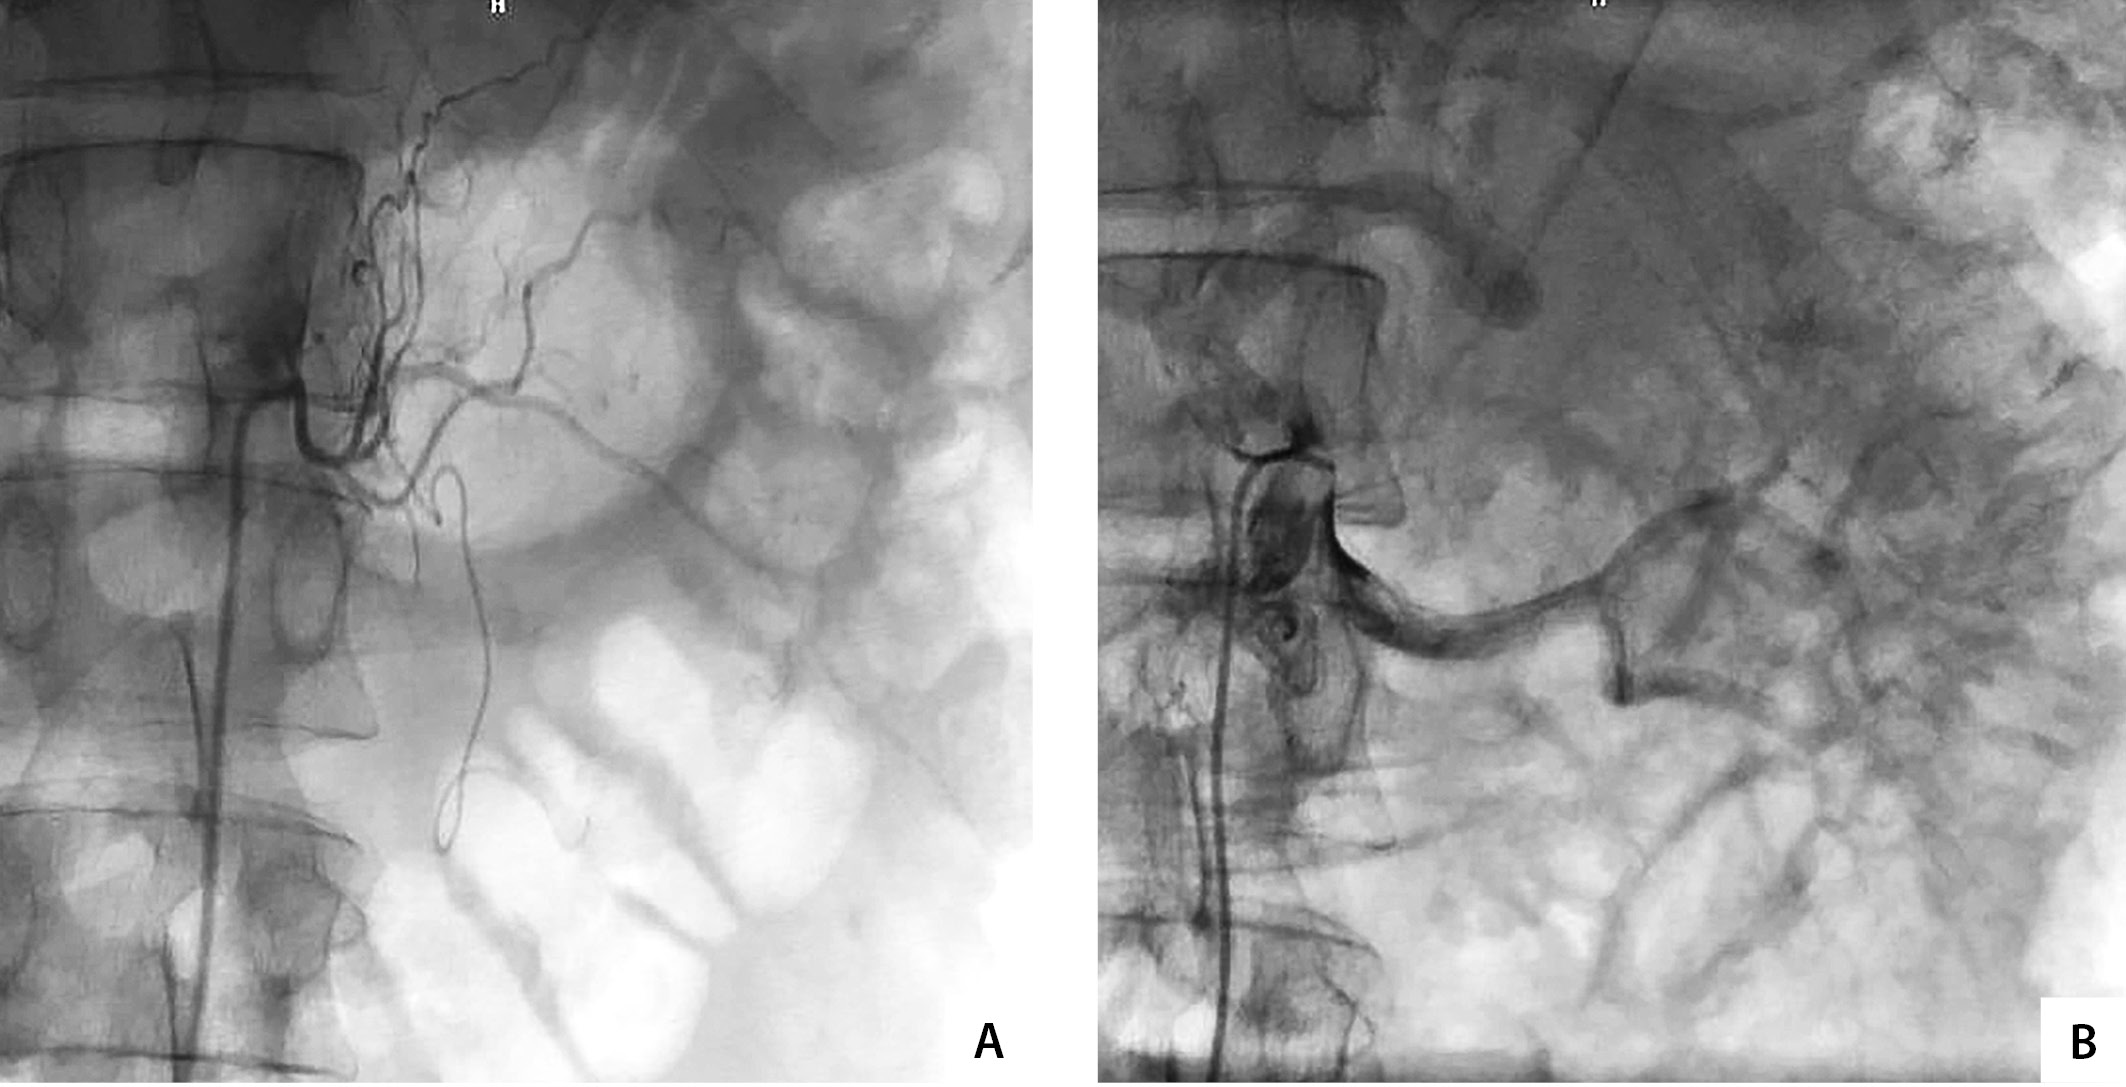

В связи с наличием у пациента феохромоцитомы больших размеров, злокачественной артериальной гипертензии, трудно поддающейся медикаментозной коррекции, а также принимая во внимание ранние сроки после острого нарушения мозгового кровообращения, с целью профилактики интраоперационного кровотечения и интраоперационных критических нарушений гемодинамики, а также обеспечения безопасного выполнения лапароскопической адреналэктомии принято решение о выполнении первым этапом рентгенэндоваскулярной эмболизации сосудов надпочечника. В условиях непрерывного неинвазивного мониторинга АД и частоты сердечных сокращений (ЧСС), доступом через правую общую бедренную артерию выполнено ангиографическое исследование, в ходе которого выявлено, что в проекции левого надпочечника имеется крупная опухоль с гиперваскулярным рисунком, кровоснабжаемая увеличенной в диаметре средней надпочечниковой артерией, отходящей от левой полуокружности аорты. После селективной катетеризации выполнена ее эмболизация частичками поливинилового спирта размерами от 250 до 1000 микрон. Контрольное ангиографическое исследование продемонстрировало полную редукцию кровотока в опухоли (рис. 2). Затем выполнена катетеризация правой общей бедренной вены. В ходе каваренографии выявлена значительно расширенная центральная вена левого надпочечника, типично впадающая в левую почечную вену. После селективной катетеризации вена эмболизирована двумя платиновыми спиралями Azur, при контрольном ангиографическом исследовании притоки центральной вены не контрастируются (рис. 3). В анализе суточной мочи, выполненном на следующее утро после рентгенэндоваскулярного вмешательства, отмечалось умеренное повышение уровней метилированных производных катехоламинов (метанефрин — 1414,0 мкг/сут, норметанефрин — 1512,0 мкг/сут).

Рисунок 2. Артериальный этап рентгенэндоваскулярного вмешательства: А — селективная ангиография левой средней надпочечниковой артерии; В — полная редукция кровотока в левой средней надпочечниковой артерии после эмболизации частичками поливинилалкоголя.